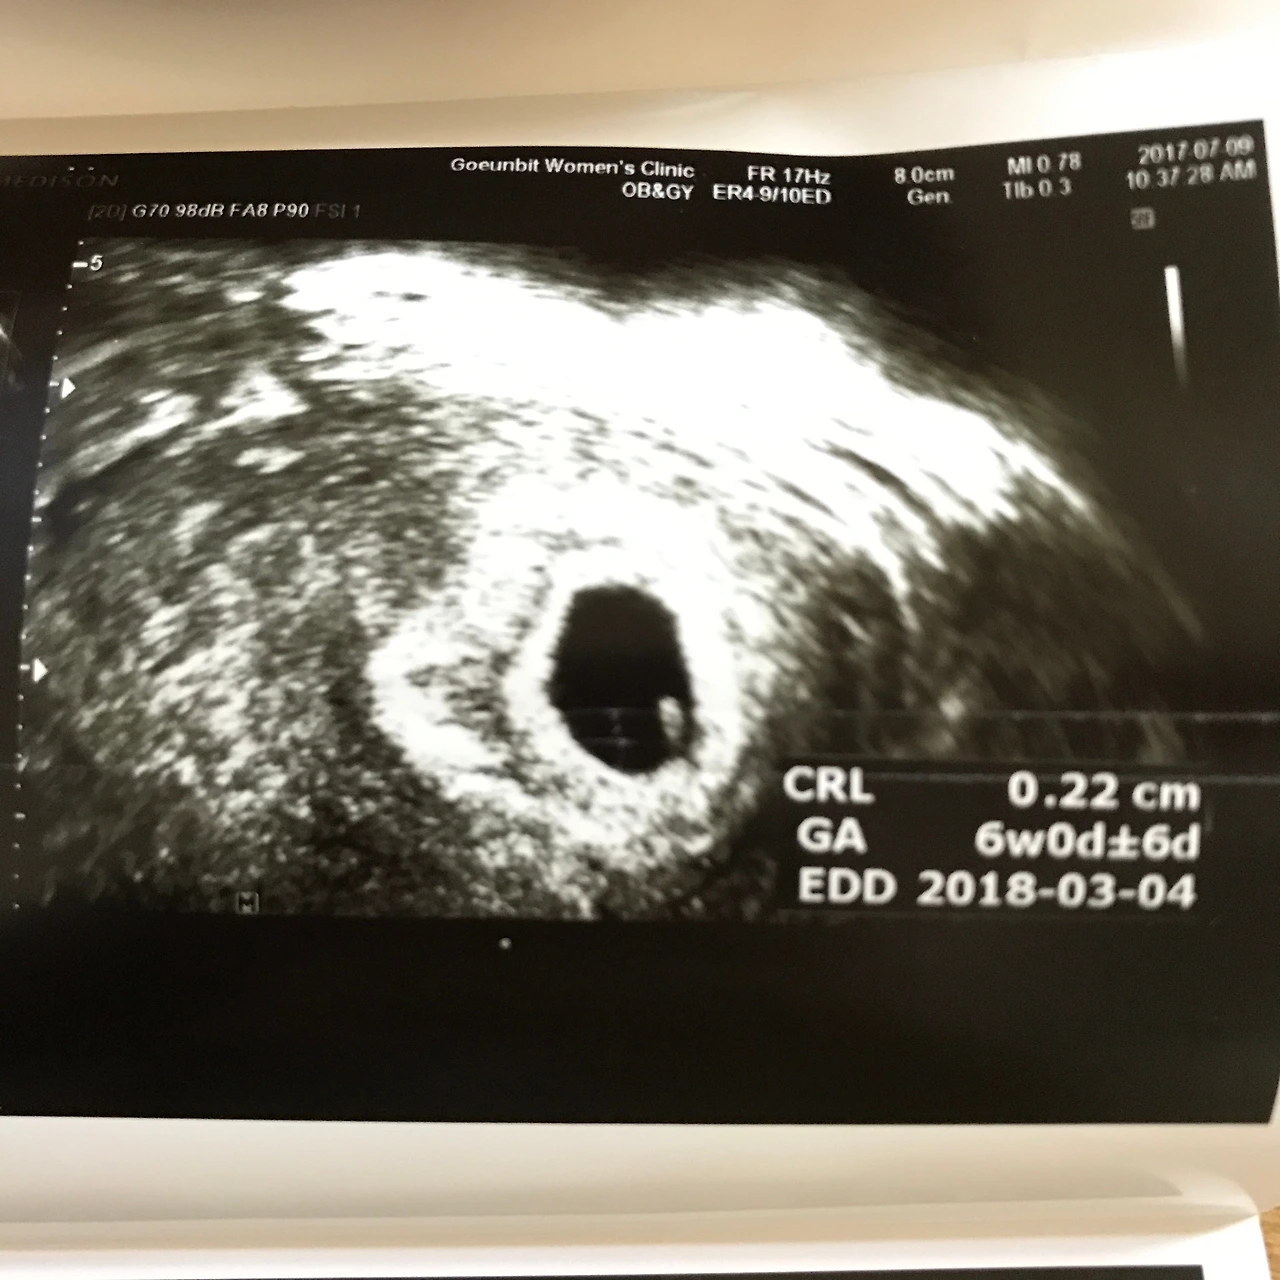

아이는 지금껏 내가 해오던 선택과는 차원이 다른 결정이었다. 물릴수도 되돌아갈수도 없다. 주변에선 아이가 있는 삶과 없는 삶은 완전히 다르다고 말했다. 들은건 많아 머리로는 아는데 직접 경험하질 않았으니 막연히 그렇게나 다를까 싶었다. 그렇게나 힘들까 싶었다. 게다가 시댁과 친정 어르들은 결혼한 지 4년동안 신혼생활을 즐기는 우리가 답답하셨는지 아이에 대한 기대를 은근 내비쳤다. 나는 주변의 시선과 압박에 자유롭지 못했다. 아이를 갖는 시기도 고민이었다. 더 늦게 아이를 낳으면? 그땐 내 공부방이 더 자리 잡을텐데? 고민과 생각이 꼬리를 물고 이어지다보니 나는 점점 지치기 시작했다. 이렇게 생각한다고 답이 나오는 것도 아니었다. 그래서 난 아주 단순한 결론에 도달했다. 어이없게도 운명에 맡기기로 한 것이다! 일단 계획을 해보고 안되면 그때 가서 다시 생각하자! 내 삶의 가장 중대한 결정을 결국 운명에 맡기기로 한 것이다. 이렇게 허무하게 우주의 결정에 따를 것을 왜 머리 터지게 고민했나 싶다. 무계획 같은 계획 임신을 진행한지 5개월이 지날 무렵..그런 철없는 나에게 아기가 찾아왔다.